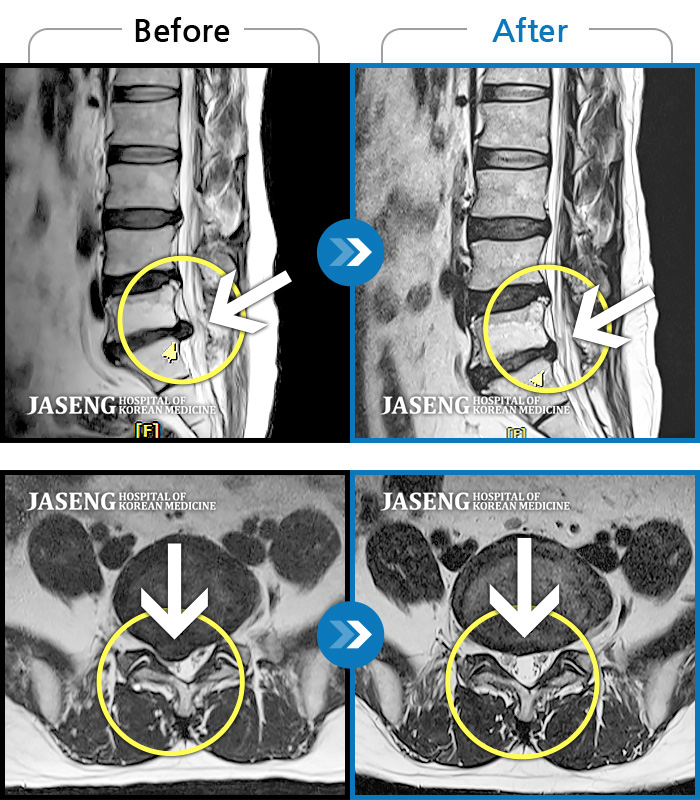

허리디스크

광주 · 장영우 원장

양측 허리부터 골반 묵직한 통증, 좌측 다리 외측까지 이어지는 당기는 통증으로 내원하셨습니다.

촬영시기

2503.04.01 ~ 2509.11.01

2025.09.22